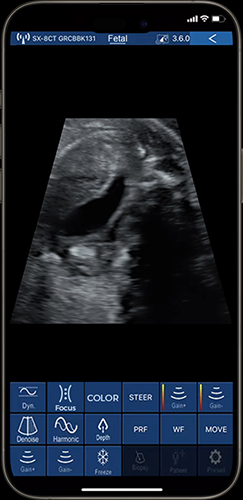

For routine mid-pregnancy obstetric scans, clinicians prefer 80-element ultrasound devices to evaluate key growth markers such as the biparietal diameter, head circumference, and limb length, which are crucial for determining gestational age and overall fetal development. The ultrasound device with 80 elements also helps clinicians visualize amniotic fluid levels, placenta location, and the presence of multiple gestations. These scans serve as an essential component of prenatal care, providing a foundational understanding of fetal development and enabling early identification of potential issues such as growth restriction or anatomical abnormalities.